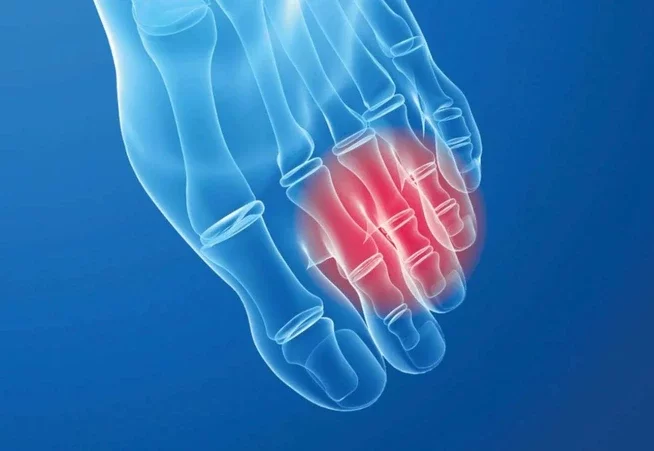

NEUROMA

Morton’s neuroma occurs when two bones rub together and compress the nerve between them. Most often, they occur between the bones leading to the third and fourth toes. It is a painful condition that makes walking difficult.

How do Orthotics Help? The full metatarsal arch maintains the natural curve and prevents the 3rd and 4th metatarsals from entrapping the nerve.